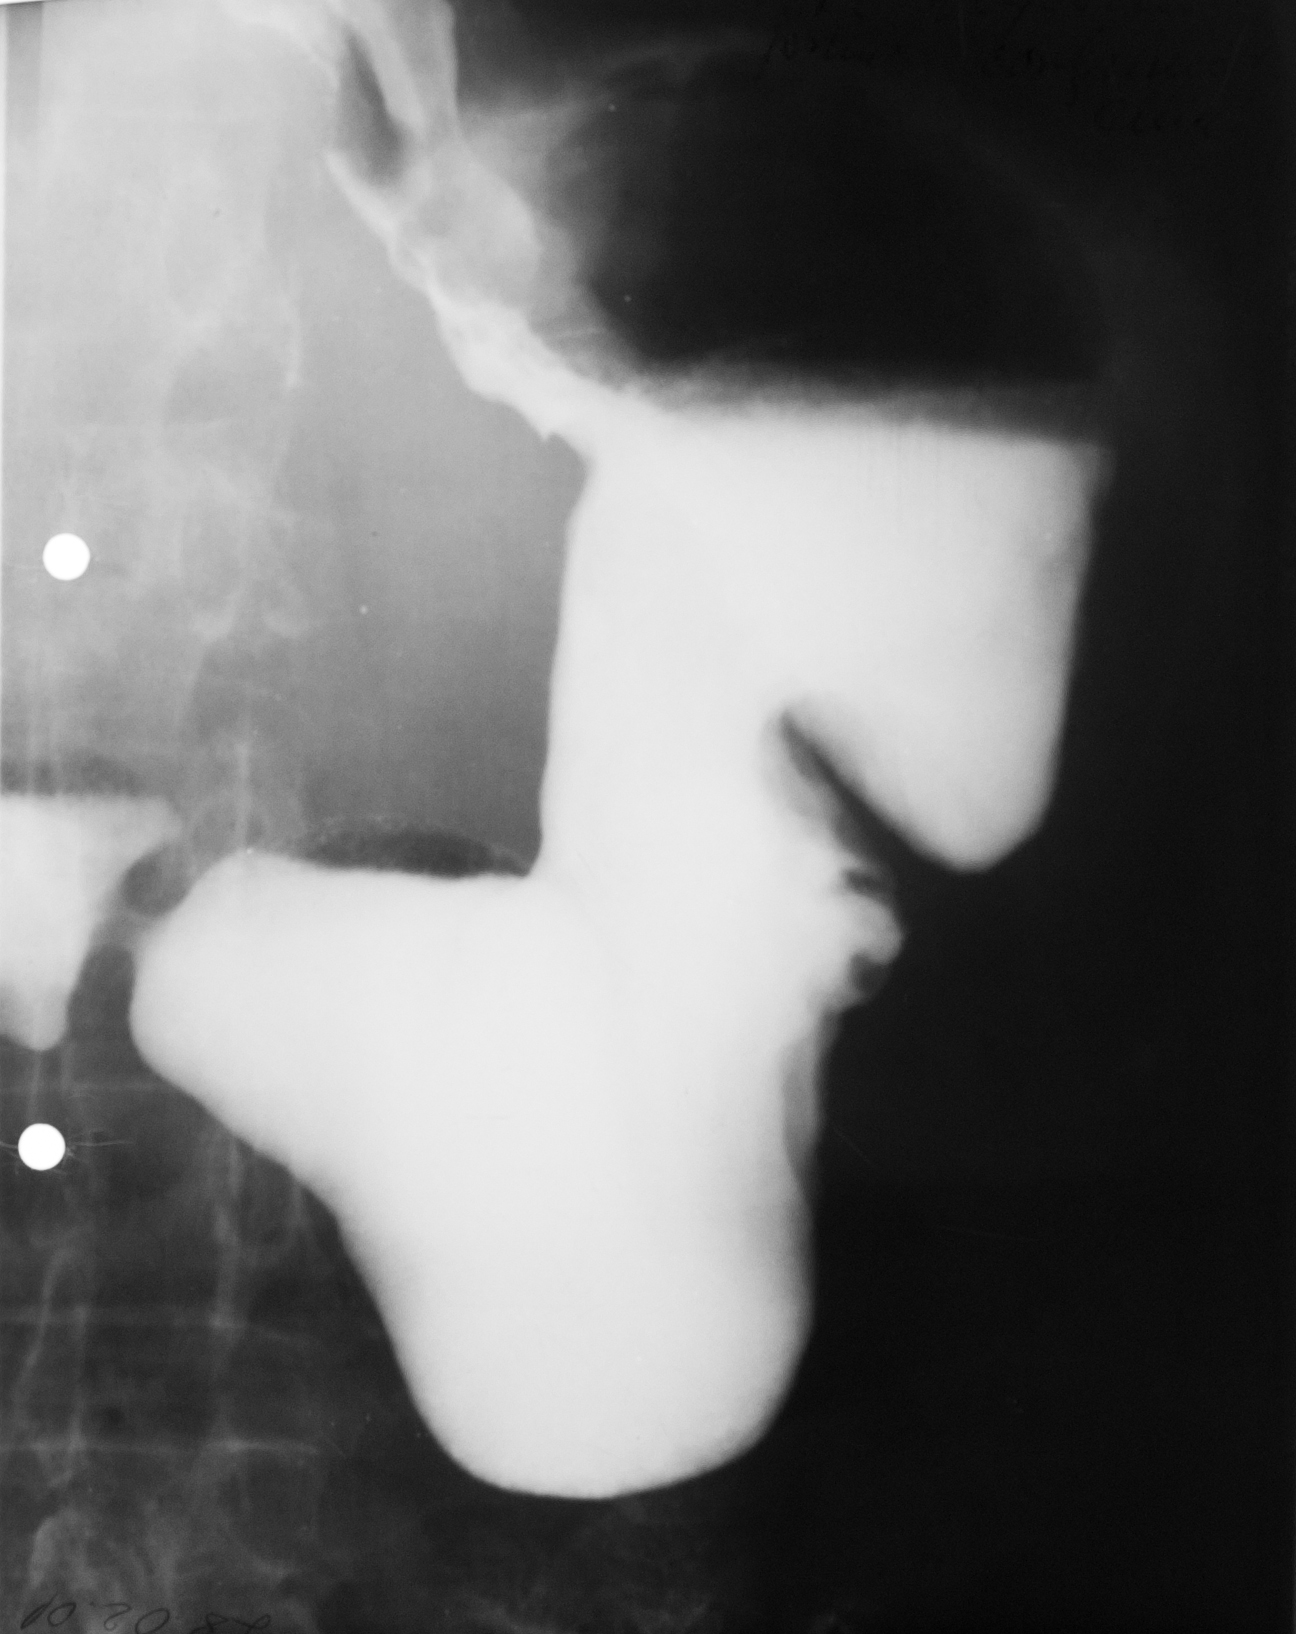

DIVERTICUL ESOFAGIAN

Tranzit baritat pe regiunea toracală

Se observă esofagul plus o imagine adiacentă a acestuia cu un camp de umplere,cu nivel orizontal și hipertransparență deasupra.

DIVERTICUL ESOFAGIAN

Tranzit baritat la nivelul esofagului.

Se observă o imagine de adiție(iese din conturul organului)

DIVERTICUL ZENKER

Tranzit baritat a esofagului pe radiografie de profil.

Se observă esofagul din profil,coloana vertebrală,imaginea de adiție cu substanță de contrast în interior și aer antidecliv

DIVERTICUL ZENKER( Văzut din față)

Pată persistentă de substanță de contrast,văzută din față,în proiecția mediastinului superior

STENOZĂ DE TIP BENIGN

Tranzit baritat la nivelul esofagului

Se observă o stenozare pe distanță mare,axială,simetrică a esofagului=Stenoză de tip benign.Se observă și o mica ulcerație:imagine de adiție triunghiulară la nivelul extremității superioare

STENOZĂ DE TIP MALIGN

Stenoză excentrică cu contur neregulat,pe o distanță mai mică

STENOZĂ DE TIP MALIGN

Contur neregulat,anfractous cu retrodilatare

Stenoză excentrică,nu este axială